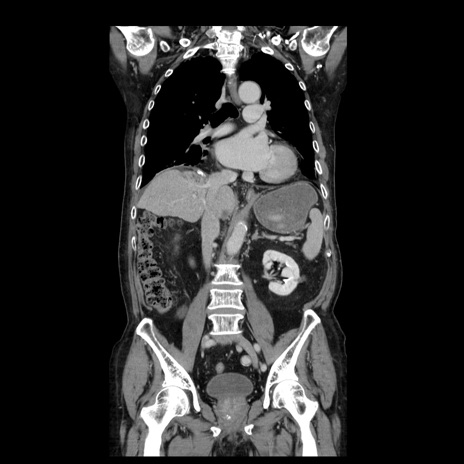

症例21(冠状断像)

【症例】70歳代男性

【主訴】腹痛

【現病歴】肝硬変・肝細胞癌にてかかりつけの方。約9時間前に食後より腹痛出現。症状が徐々に増悪し、嘔吐出現したため来院。

【既往歴】肝硬変、肝細胞癌(RFA、TACE後)

【身体所見】意識清明、表情苦悶様、BT 36℃、BP 129/78mmHg、P 88bpm、SpO2 97%(RA)、右上腹部から心窩部にかけて圧痛あり、反跳痛なし、筋性防御あり。

【データ】WBC 5800、CRP 0.16